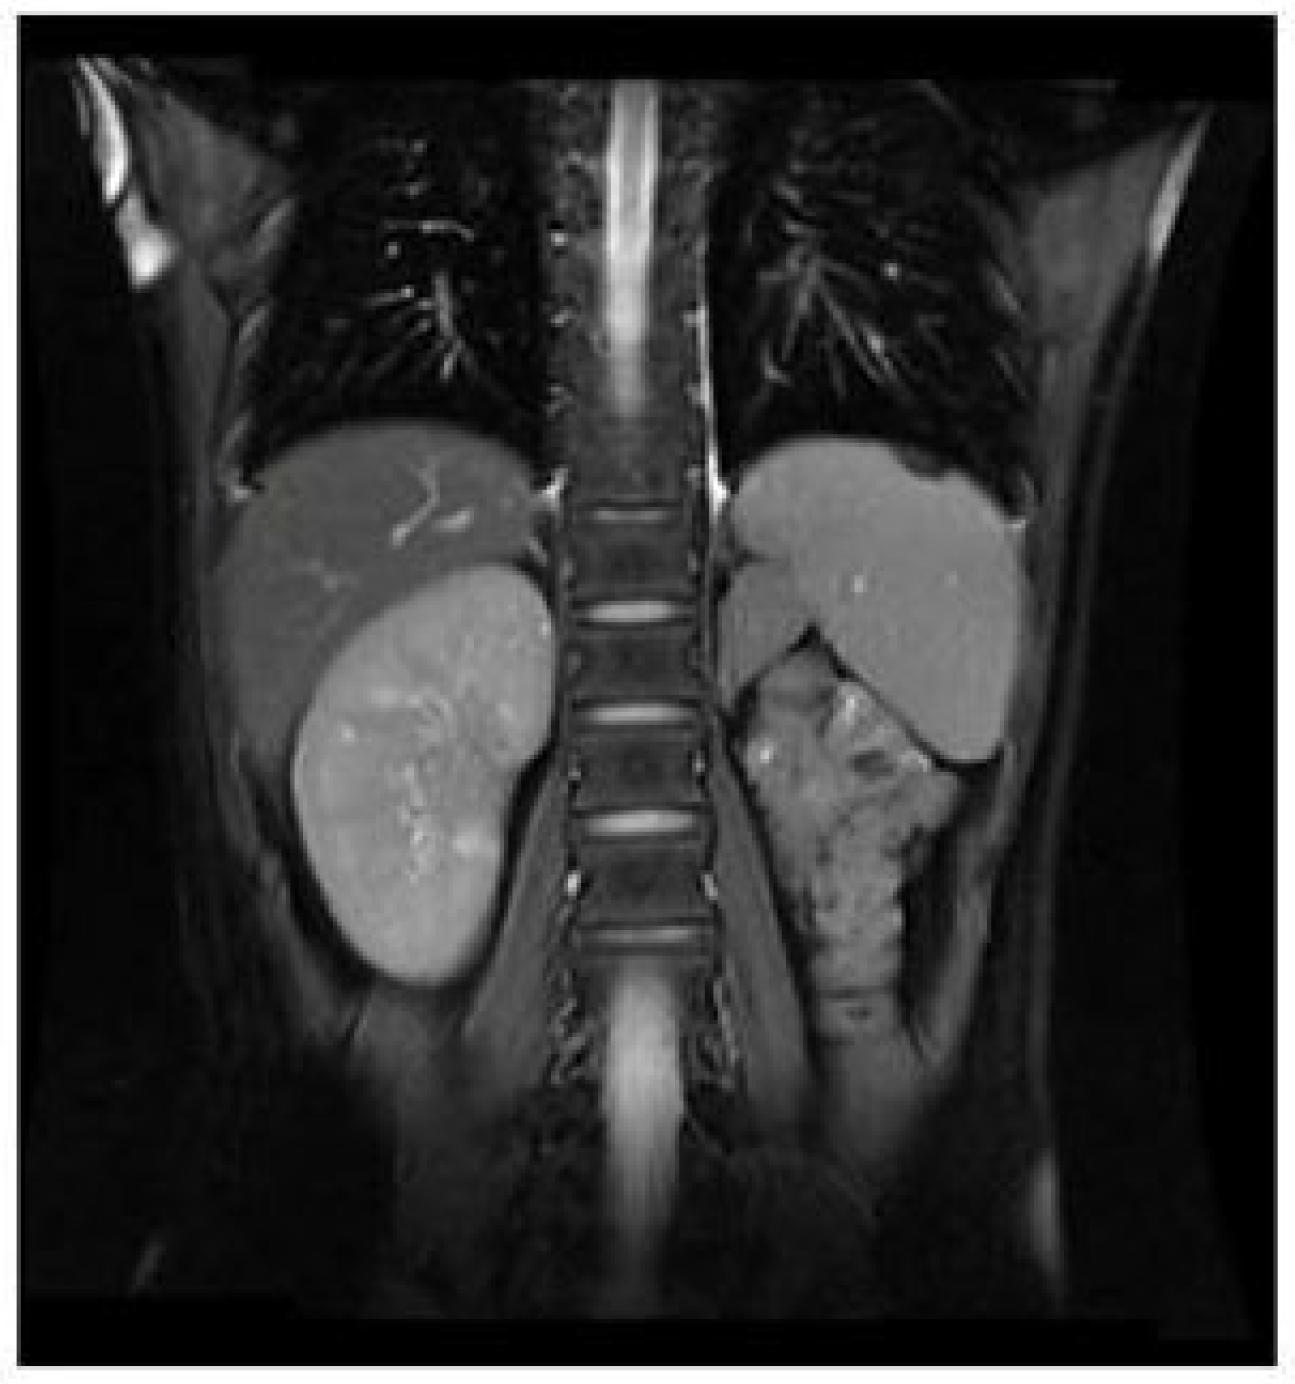

MRI demonstrated the atrophy of left kidney.

The diagnostic tests for ectopic ureter were diverse, including ultrasound, CT, MRI, and urography. The diagnostic sensitivity and specificity of each imaging test for ectopic ureter are currently uncertain. In previous case reports, ectopic ureter was diagnosed through an MRU [10], CTU [2,11], or IVP (intravenous pyelogram) [12]. Case 1 was diagnosed with an ectopic ureter using transvaginal and urethral ultrasonography due to a cystic mass at the ectopic vaginal opening of the ureter. In Case 2, the ectopic ureter was diagnosed with both a pelvic MRI and ascending urography. It has been reported that an MRU shows high accuracy in assessing ectopic ureters [13]. In Case 2, the pelvic MRI was confirmed to be the correct diagnosis. However, the abdominal MRI mistakenly interpreted the left dilated ectopic ureter as a left hematosalpinx. An MRU was also applied in Case 3 and correctly diagnosed in Case 3. Excluding the ectopic orifice, abnormalities of the kidney and ureter in all cases were diagnosed using ultrasound.